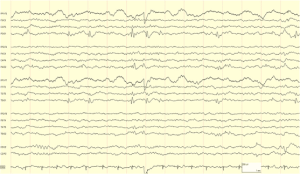

Take our EEG Test Questions!

Are you prepping for your EEG boards? 🧠📚

Do you just like engaging in posts about the NDT field? ✔

Engage with our community and enhance your knowledge in the neurodiagnostic field with our EEG Fun Facts. Each fact comes with a question and multiple choice answer to choose from to test your knowledge!